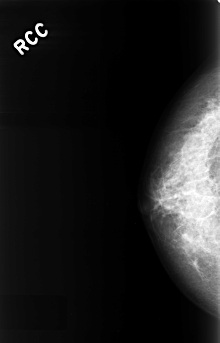

ics_version 1.0 filename C-0323-1 DATE_OF_STUDY 1 2 1995 PATIENT_AGE 48 FILM FILM_TYPE REGULAR DENSITY 4 DATE_DIGITIZED 8 10 1998 DIGITIZER LUMISYS LASER SEQUENCE LEFT_CC LINES 4528 PIXELS_PER_LINE 2984 BITS_PER_PIXEL 12 RESOLUTION 50 OVERLAY LEFT_MLO LINES 4352 PIXELS_PER_LINE 2824 BITS_PER_PIXEL 12 RESOLUTION 50 OVERLAY RIGHT_CC LINES 4448 PIXELS_PER_LINE 2848 BITS_PER_PIXEL 12 RESOLUTION 50 NON_OVERLAY RIGHT_MLO LINES 4384 PIXELS_PER_LINE 2784 BITS_PER_PIXEL 12 RESOLUTION 50 NON_OVERLAY |

FILE: C_0323_1.LEFT_CC.OVERLAY TOTAL_ABNORMALITIES 1 ABNORMALITY 1 LESION_TYPE MASS SHAPE ROUND MARGINS OBSCURED ASSESSMENT 4 SUBTLETY 5 PATHOLOGY BENIGN TOTAL_OUTLINES 1 BOUNDARY |